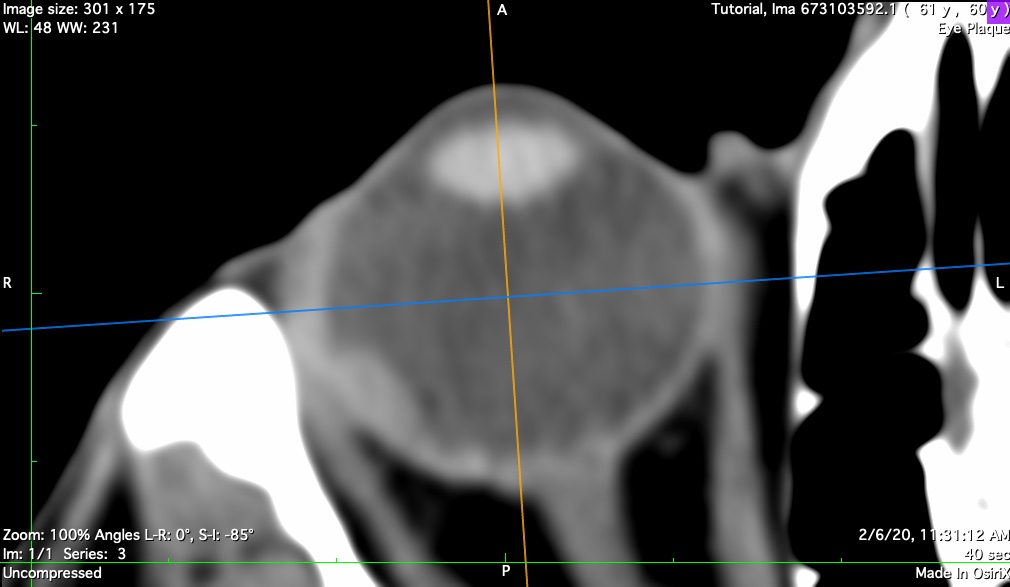

nerve

Coronal plane through the posterior sclera and optic nerve. This reconstruction helps to approximate the center of the optic disc and the diameter of the sheath surrounding the optic nerve. The sheath diameter determines how closely the plaque shell and seeds can approach the disc. This distance becomes important for extremely posterior and peripapillary tumors.

n-axial

Axial bisector illustrating the nerve-coronal plane (blue axis)